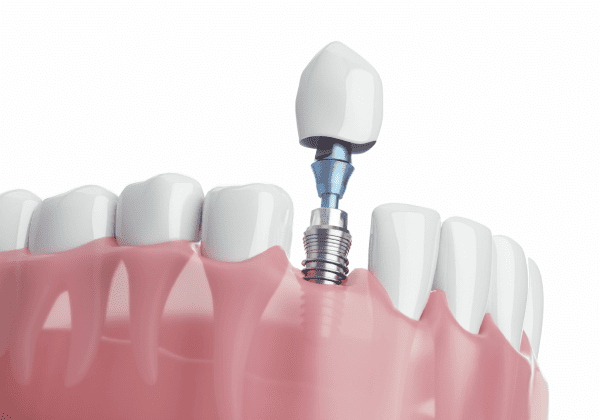

代表的な再生療法のひとつが「GBR(骨誘導再生法)」です。骨が不足した部位に自家骨や人工骨を補填し、特殊な膜(メンブレン)で覆うことで、骨の再生を促しインプラントの土台を築く方法です。

また、上顎奥歯など骨が特に薄い部位には「サイナスリフト(上顎洞底挙上術)」が適応されます。上顎洞と呼ばれる空洞の底を持ち上げ、その下に骨を造成することで、十分なインプラント埋入スペースを確保することが可能になります。

これは、虫歯や歯周病などで抜歯が必要になった際、その当日にインプラントを埋め込む方法です。従来であれば、抜歯後に歯ぐきや骨の治癒を数ヶ月待ったうえで次のステップへ進んでいましたが、この方法を用いることで、治療期間を短縮できるほか、手術の回数も抑えられます。